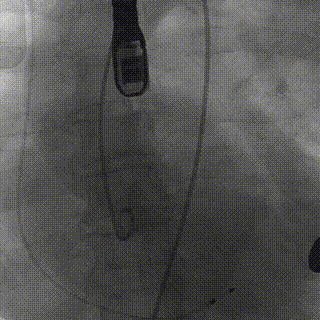

球囊预扩张:25mm球囊扩张可见轻微腰征,左冠瓣叶被完全推起来并超过左冠开口。